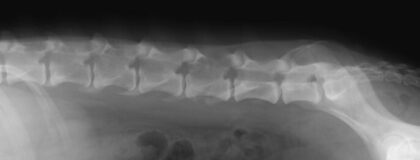

Online-Seminar: Röntgen der Wirbelsäule beim Kleintier

In den Zeiten von CT und MRT entsteht mitunter der Eindruck, dass das gute alte Röntgen in der Diagnostik neurologischer Erkrankungen ausgedient hat. In diesem vetinar erfahren Sie, dass dies mitnichten der Fall ist. Ja, es gibt viele Erkrankungen von Wirbelsäule und Rückenmark, die einer Schnittbilddiagnostik bedürfen, doch es gibt andere, die sich im nativen Röntgen diagnostizieren lassen. Um letztere Erkrankungen geht es in diesem vetinar.